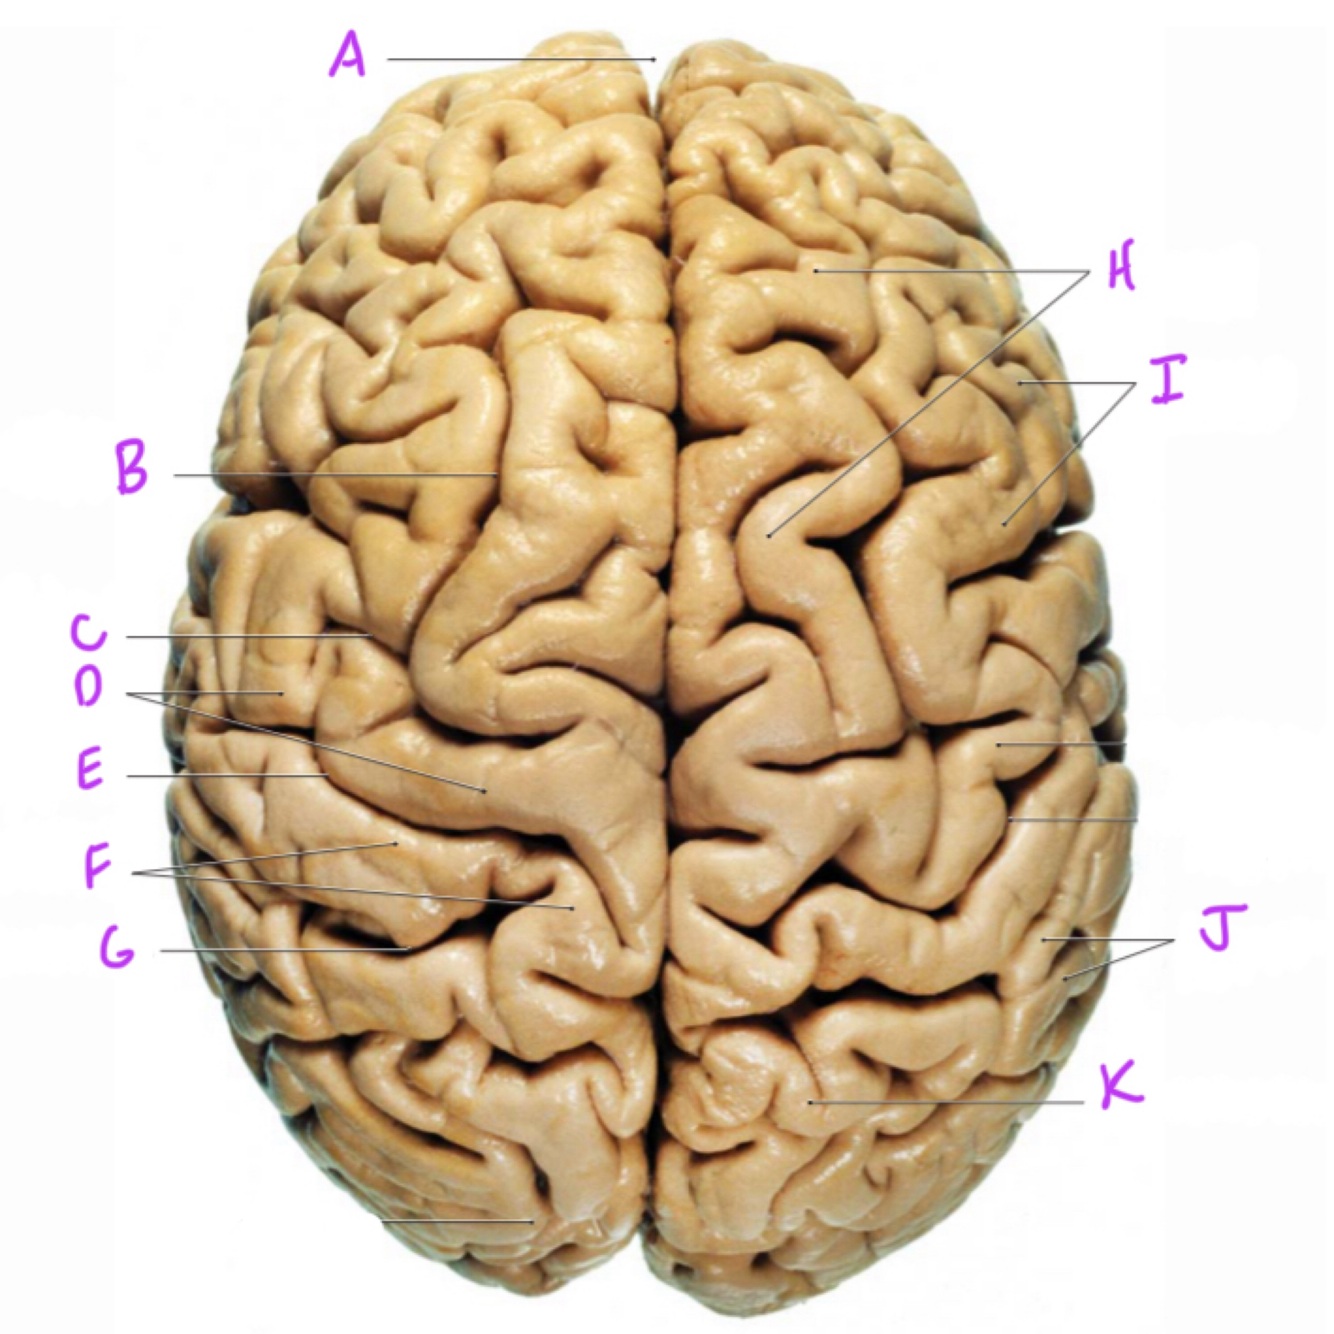

Q

A

longitudinal fissure

10

B

superior frontal sulcus

11

C

precentral sulcus

12

D

precentral gyrus

13

E

central sulcus

14

F

postcentral gyrus

15

G

postcentral sulcus

16

H

superior frontal gyrus

17

I (i)

middle frontal gyrus

18

J

supramarginal gyrus

19

K

superior parietal lobule